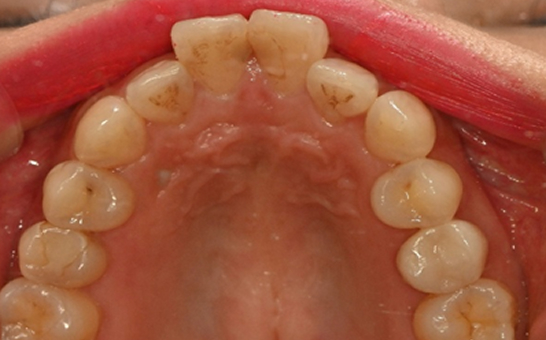

※ 바른선택치과의원은 의료법을 준수하며 위 케이스는 실제 내원 환자분의 동의하에 공개된 사진과 동일한 환자분께 같은 조건에서 촬영한 사진을 활용했습니다.

개인에 따라 진료 및 치료 방법이 다르게 적용할 수 있으며, 효과와 부작용이 개인마다 다르게 나타날 수 있는 점을 안내해 드리며, 진료 전 전문의료진과 충분한 상담을 권해드립니다.